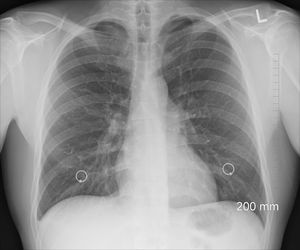

Lunge: H2O2 schwächt das Gewebe im menschlichen Körper (Foto: Pixabay, oracast) |